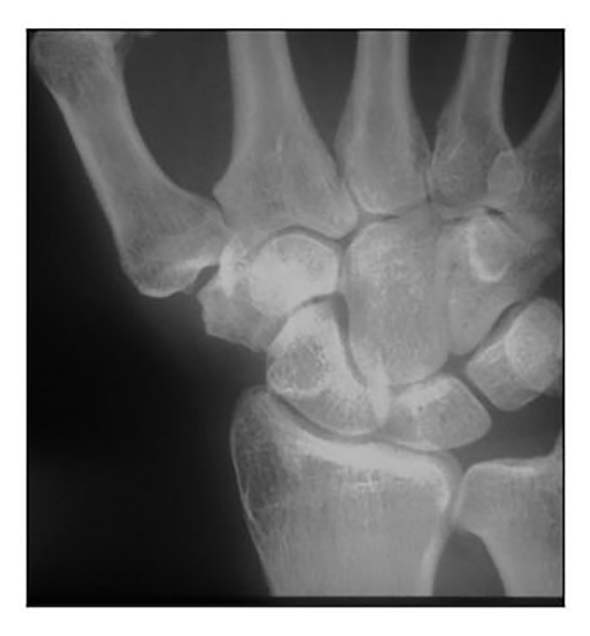

Die Rhizarthrose gehört zum rheumatischen Formenkreis und macht sich je nach Stadium durch eine sehr schmerzhafte zunehmende arthrotische Zerstörung des Daumensattelgelenkes bemerkbar. Nach einer Untersuchung von Pellegrini 1 erkranken Frauen 10- bis 15-mal häufiger an Rhizarthrose als Männer. Das deckt sich mit den Erfahrungen des Autors aus den Evaluierungsübersichten von fast 4.000 Patientinnen und Patienten mit dem durchschnittlichen Verhältnis von 13:1 zugunsten der Patientinnen. Die Rhizarthrose tritt bei Frauen nach den Erfahrungen des Autors ca. 3 Jahre nach dem Beginn der Menopause auf und ist vermutlich genetisch bedingt: Nur zwei Prozent der Patientinnen des Autors erwähnten in der Anamnese, keine Schwangerschaft gehabt zu haben. Auslöser für die Rhizarthrose bei Männern ist in den meisten Fällen eine traumatisch bedingte Verletzung des Daumensattelgelenkes („Skidaumen“) oder eine ständige berufliche Überbeanspruchung, zum Beispiel bei Vibrationen durch Maschinen oder auch durch handschriftliches Schreiben in Büroberufen. Die Rhizarthrose tritt nach Eaton/Littler radiologisch klassifiziert in vier Stadien auf (Abb. 1) 2:

- Stadium I: normale Gelenkkonturen, erweiterter Gelenkspalt (Erguss)

- Stadium II: geringe Gelenkspaltverschmälerung, evtl. vorhandene Gelenktrümmer kleiner als 2 mm

- Stadium III: sklerotische und zystische Veränderungen im subchondralen Knochen, Osteophyten größer als 2 mm, Zerstörung des Daumensattelgelenkes, normale trapezioskaphoidale Gelenkfläche

- Stadium IV: zusätzlich zum Verschleiß der trapeziometakarpalen Gelenkfläche degenerative Veränderungen im Bereich der trapezioskaphoidalen Gelenkfläche

Die Patienten geben bereits beim Stadium I Schmerzen beim Pinzettengriff und/oder beim kleinen oder großen Rundgriff an. Häufig treten die ersten Schmerzen beim Schwenken der Daumen zur volaren Handfläche auf. Beim Stadium II treten die Subluxationsstellung im Daumensattelgelenk und eine temporäre Schmerzhaftigkeit bei vielen Tätigkeiten sowie häufig auch in Ruhe auf. Im Stadium III findet sich eine deutliche Luxierung des Daumensattelgelenkes und eine beginnende Proximalisierung des Mittelhandknochens des Daumens. Zusätzlich geben die Patientinnen und Patienten eine Schmerzhaftigkeit auch bei bereits geringen Bewegungen an. Häufig wird auch über Nachtschlafstörungen beim Greifen nach dem Kopfkissen oder dem Oberbett geklagt. Im Stadium IV finden sich ebenfalls eine deutliche Luxierung des Daumensattelgelenkes, eine deutliche Proximalisierung des Daumenmittelhandknochens und eine Schmerzhaftigkeit auch bei bereits geringen Bewegungen. Häufig findet man eine Fehlstellung des Daumens im Daumengrundgelenk. Oft ist zunächst die sekundäre Hand – beim Rechtshänder das linke Daumensattelgelenk, beim Linkshänder umgekehrt – von der Rhizarthrose betroffen. 18 Prozent der versorgten Patienten litten an einer zu versorgenden doppelseitigen Rhizarthrose. Durch einen vom Autor 2010 entwickelten Testgriff – ähnlich dem Ansatz des Daumens beim Händeschütteln – durch Druck des Daumens der Patienten in die Tabatiere des Behandlers kann festgestellt werden, bei welchem Druck der Schmerz einsetzt.